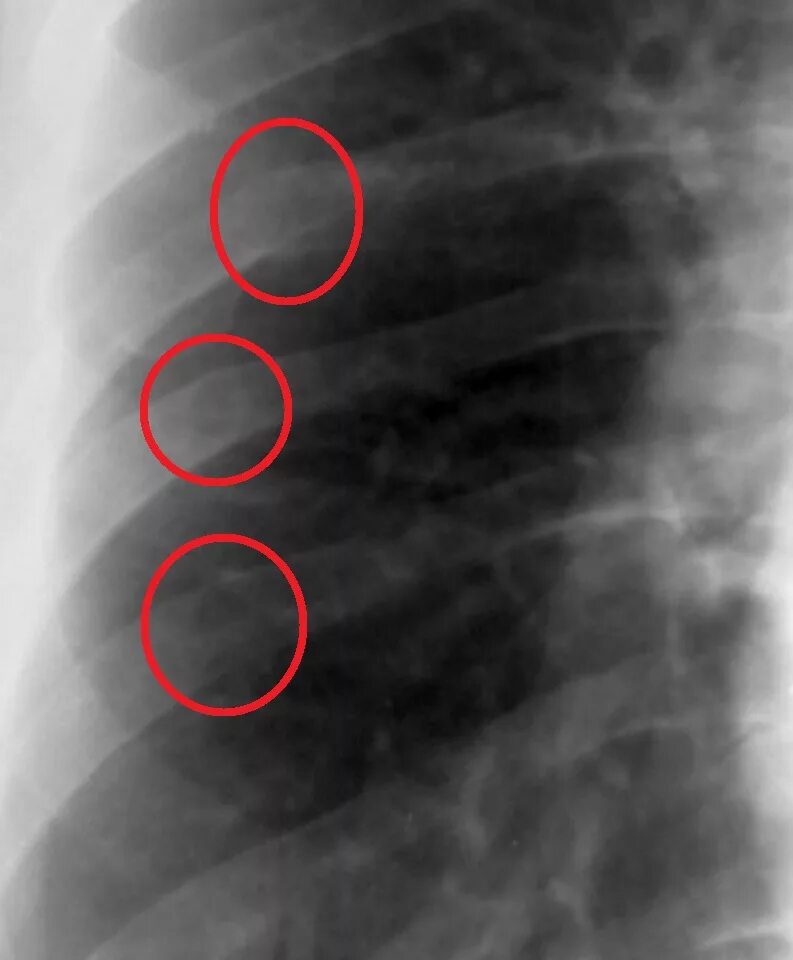

Как определить перелом ребра или ушиб